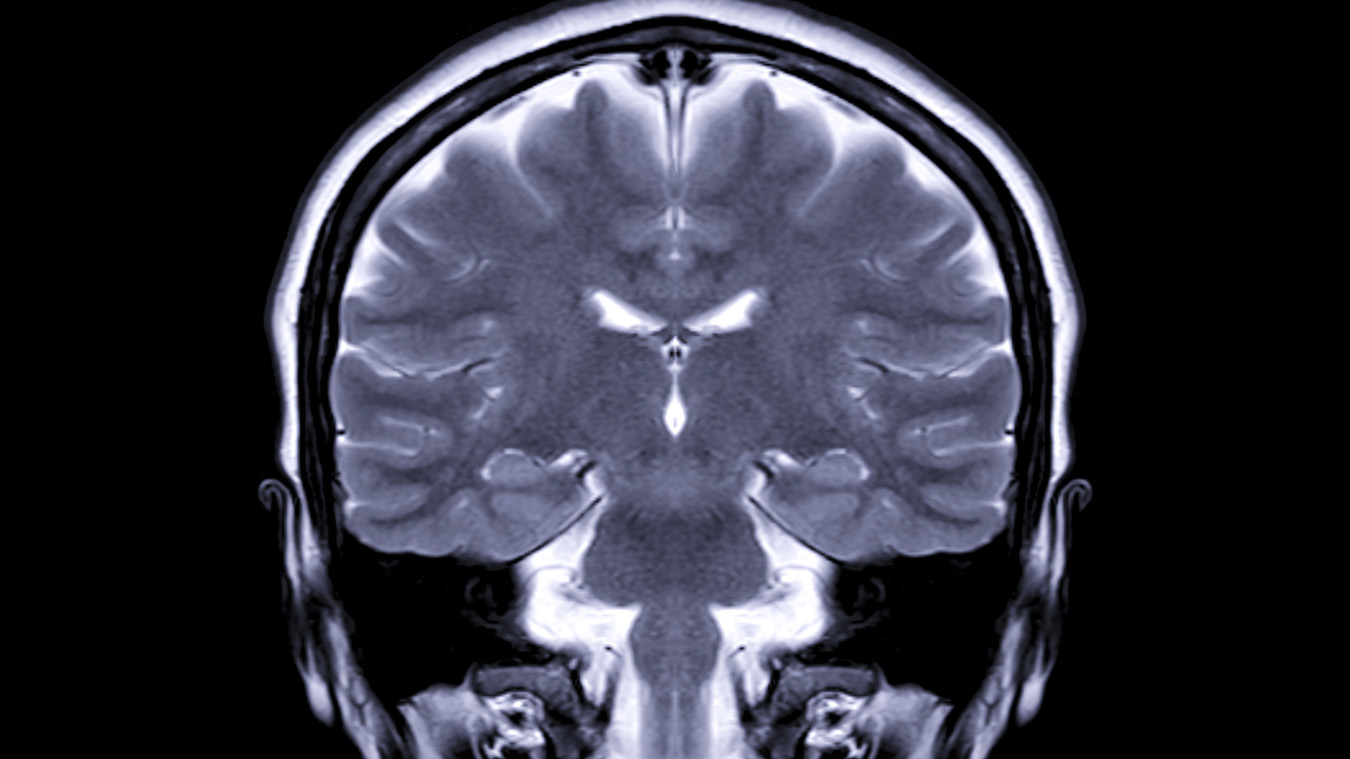

يجري نقاش آخر بين المتخصصين، مع اتساع الفجوة بين أوروبا والولايات المتحدة: كيف يتم تشخيص مرض ألزهايمر؟

سُجّل تقدم كبير في تسهيل التشخيص من خلال اختبار دم بسيط يحدّد «المؤشرات البيولوجية» لآليات الدماغ المُرتبطة بالمرض.

يُمثّل ذلك ثورة مقارنة بالاختبارات الحالية التي تُعدّ متعبة ومُكلفة لعدد كبير من المرضى، مثل البزل القطني.